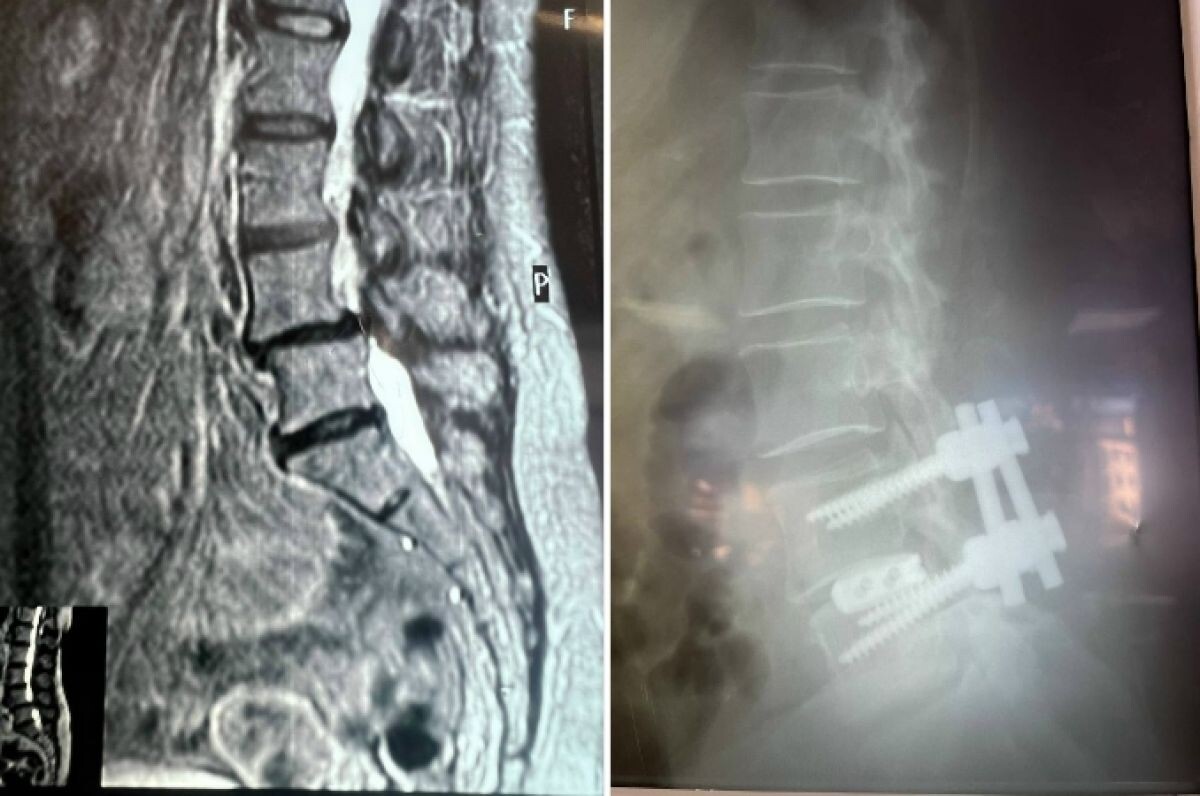

В Воронежской городской клинической больнице №11 нейрохирурги провели сложную операцию, которая вернула пациентке способность ходить без мучительной боли. Об этом сообщили в региональном минздраве. В начале марта в отделение поступила женщина с жалобами на сильную боль в пояснице и ногах, онемение при ходьбе и резкое ограничение движений. Обследование выявило множество проблем: поражение межпозвоночных дисков, сужение позвоночного канала на уровне 4–5 поясничных позвонков и другие патологии. Год консервативного лечения не дал результатов. В последние месяцы боль только усиливалась, ходить становилось все труднее. В больнице предложили декомпрессивно-стабилизирующую операцию. Хирурги «разжали» позвонки с двух сторон, удалили грыжу и поврежденные диски, заменив их имплантами. С помощью микрохирургической техники сняли давление на оболочку спинного мозга и нервные корешки. Затем исправили смещенный позвонок и установили конструкцию из четырех титановых винтов и двух балок для стабилизации

В больнице предложили декомпрессивно-стабилизирующую операцию. Хирурги «разжали» позвонки с двух сторон, удалили грыжу и поврежденные диски, заменив их имплантами. С помощью микрохирургической техники сняли давление на оболочку спинного мозга и нервные корешки. Затем исправили смещенный позвонок и установили конструкцию из четырех титановых винтов и двух балок для стабилизации.